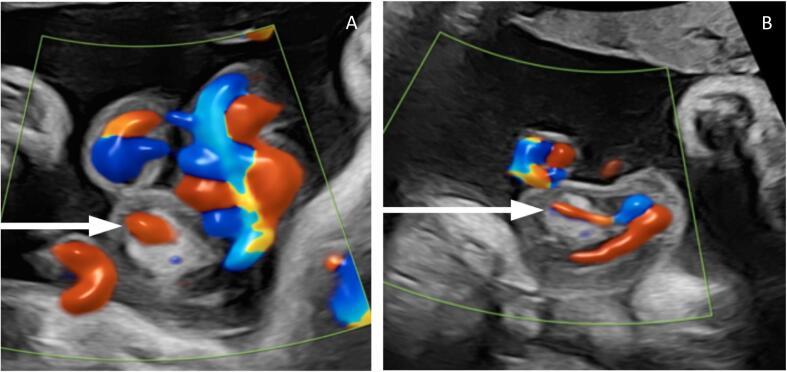

Umbilical cord hemangiomas are rare benign vascular anomalies with limited documentation in the literature. Given their association with adverse perinatal outcomes, standardised criteria for reporting and monitoring are needed. This case report presents an instance of umbilical cord hemangioma and proposes a structured framework for future documentation. A comprehensive literature review using OVID Medline and Embase identified cases of umbilical cord hemangiomas, their clinical presentations, and maternal and neonatal outcomes. A case diagnosed in the third trimester is presented, detailing antenatal surveillance, histopathological findings, and perinatal outcomes. Key parameters were analysed in the context of the literature to inform standardised reporting criteria. A 36-year-old woman (G3P2) was diagnosed with an umbilical cord hemangioma at 29 + 3 weeks gestation following a routine growth scan. Serial ultrasound scans demonstrated lesion stability until 35 + 4 weeks, prompting increased fetal surveillance. Multidisciplinary consensus favoured expectant management, leading to an uncomplicated spontaneous vaginal delivery at 39 weeks. Histopathology confirmed a cord hemangioma composed of dilated, ectatic vascular channels lined by endothelial cells. This case contributes to the growing body of evidence on umbilical cord hemangiomas by providing detailed clinical, ultrasound, and histopathological findings. Successful expectant management and favourable perinatal outcomes highlight the role of serial ultrasound surveillance. Given the rarity and potential risks of these lesions, standardised reporting is essential to improve understanding and to guide management. By proposing a set of standardised reporting criteria, this case report serves as a step toward enhancing data consistency and informing management strategies.